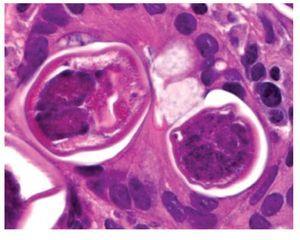

Mujer de 74 años de edad, residente del Distrito Federal, con antecedente de esclerodermia y cirrosis biliar primaria en tratamiento con ácido ursodeoxicólico. Inició ocho días previos a su ingreso con dolor abdominal epigástrico, náusea, distensión abdominal y melena. A la exploración física se encontró con signos vitales normales, mucosas pálidas, peristaltismo disminuido, sin otros hallazgos relevantes. Los exámenes de laboratorio mostraron hemoglobina 10.6 gr/dL, hematocrito 31%, leucocitos totales 8700 células/dL (4% de eosinófilos). Se le realizó endoscopia de tubo digestivo, que evidenció esofagitis erosiva grave, gastropatía eritematosa petequial, múltiples úlceras gástricas de 10 mm de diámetro con base de fibrina (Figura 1) y duodenitis erosiva (Figura 2). Se tomaron biopsias de los bordes de las ulceras y se envió en formol a estudio histopatológico que informó estrongiloidiasis gástrica, con inflamación crónica y aguda sin Helicobacter pylori (Figuras 3 y 4).

¿ Figura 4. Hematoxilina-eosina: Estrongiloidiadis gástrica.